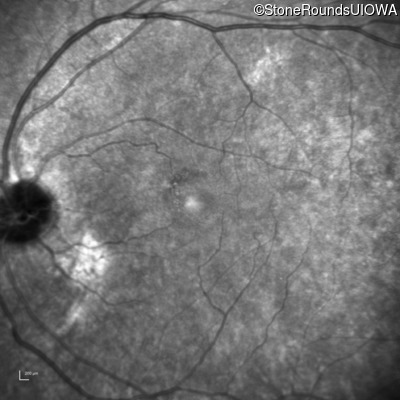

This 44 year old man became photophobic about 6 years ago. He has been taking Imuran since his kidney transplant 23 years ago.

| Senior-Loken Syndrome | NPHP1 | Gly343Arg G(GG)>A(GG) | Deletion of Entire Gene | AR |